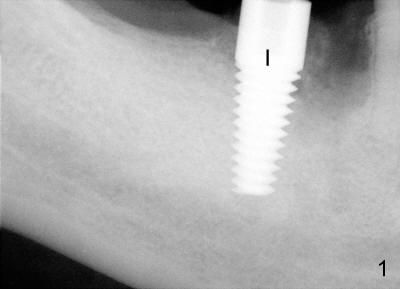

Fourteen days after placement of Tatum tapered implant (6x17 mm) in #30 edentulous area (Fig.1: I), an acute infection develops buccal to supragingivally placed implant (Fig.2: *). Why?

In fact, the inferior alveolar nerve (IAN) was injured during osteotomy. Although the implant was placed without impingement upon the nerve, it was placed supragingivally (Fig.2: I). Medrol dose pack was prescribed. The patient was reluctant to take pain reliever or antibiotic. Mouth rinse was not suggested.